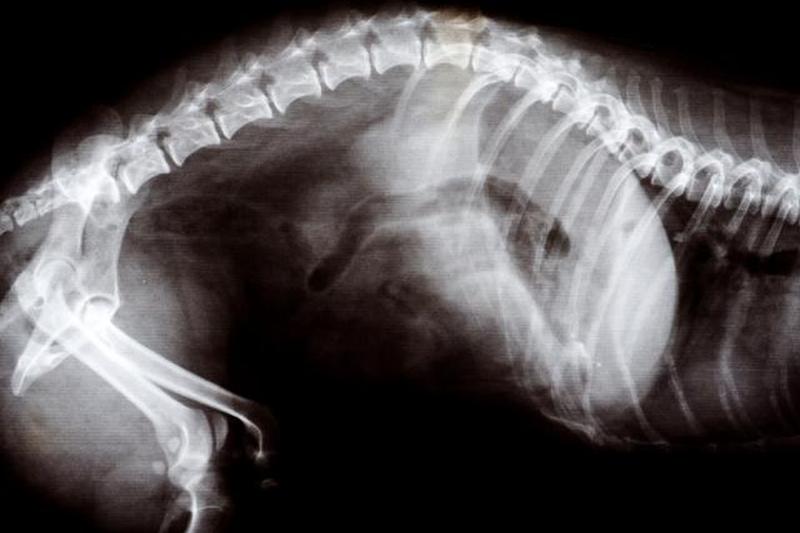

Изображение слева — это рентгеновский снимок беременной кошки на поздних сроках.